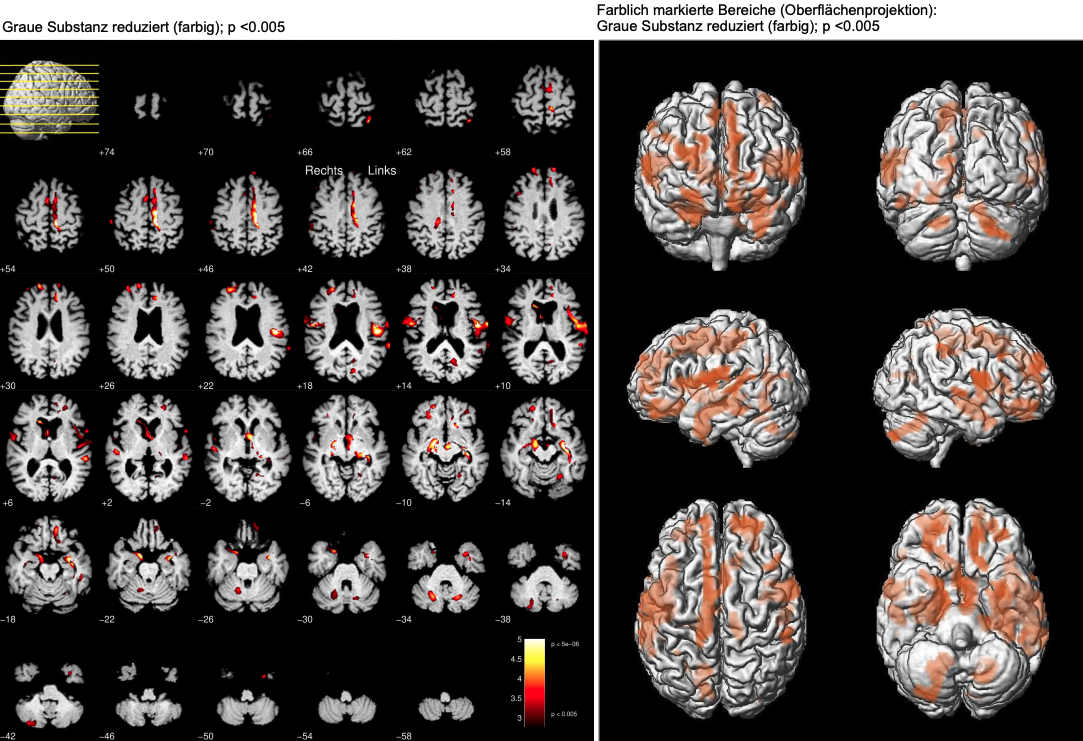

Focal brain volume loss

To identify focal brain atrophy we use the method of voxel-based morphometry, in which a comparison with a normative database is made for each pixel. This enables a very detailed overview of atrophic brain structures and is therefore particularly suitable for dementia differential diagnosis [5].

Areas with reduced grey matter highlighted in colour